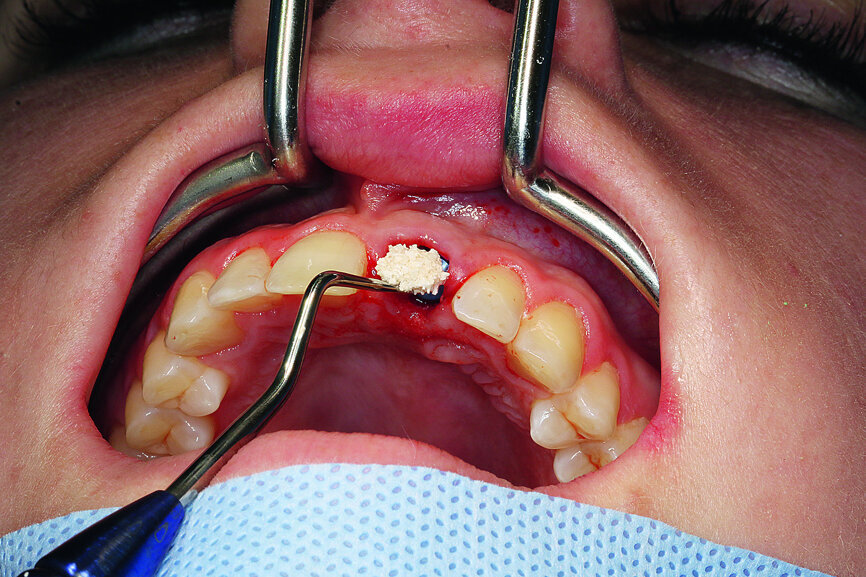

Fig. 1: Single-tooth exposure of tooth #21 after recurrent marginal gingivitis. Owing to the initial diagnosis of extensive resorption, the tooth could not be preserved.

Fig. 7: Gentle extraction preserving the vestibular lamina.

Fig. 8: The resorption of tooth #21, external view. This confirmed the accuracy of the diagnosis from

the imaging procedure.

Fig. 9: Preparing the implant bed according to the recommended drill sequence, insertion of the implant using the SICAT surgical guide.

Fig. 10: Intra-op CEREC scanning with a ScanPost.

Fig. 11: Augmentation of the vestibular alveolus.

When extracting tooth #21, it was important to preserve the vestibular lamina to allow immediate implantation. For this reason, the Sharpey’s fibres were carefully severed with a periotome, and the tooth was gently removed (Fig. 7). The tooth had pronounced dentinal resorption, confirming the previously made diagnosis (Fig. 8). The SiroLaser Blue (Dentsply Sirona) with a wavelength of 970 nm was used to disinfect the alveolus. An OsseoSpeed EV 4.8–15 mm implant (Astra Tech Implant System, Dentsply Sirona) was inserted immediately using a surgical guide (SICAT OPTIGUIDE, SICAT; Fig. 9). At > 35 Ncm, sufficient primary stability was achieved.

After the intraoperative scan with a ScanPost (Dentsply Sirona) to complete the temporary restoration, the vestibular alveolus was filled with a bone substitute material (Figs. 10 & 11).